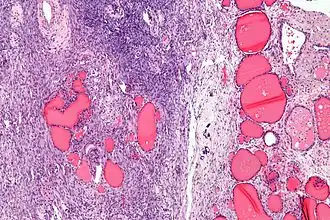

![]() Micrografía de un struma ovarii. Caracteristicamente folículos tiroides son vistos a la derecha, y estroma de ovario a la izquierda. H&E stain. | ||

Macroscópicamente, aparece un tumor nodular, sólido, parcialmente quístico, con una superficie brillante y leonada. Los hallazgos histológicos incluyen tejido tiroideo maduro con folículos normales o atróficos, que están recubiertos principalmente por tirocitos aplanados y rellenos de coloide. Aunque el tejido tiroideo es detectable en el 5-15% de los teratomas maduros, debe representar al menos el 50% del tumor para justificar el diagnóstico de bocio ovárico. A menudo hay áreas de tejido papilar en proliferación similar al adenoma, que deben diferenciarse de un carcinoma papilar de tiroides por diagnóstico diferencial. El tejido conjuntivo circundante muestra esclerosis cicatrizada y puede contener folículos linfoides y células inflamatorias.[2][4]